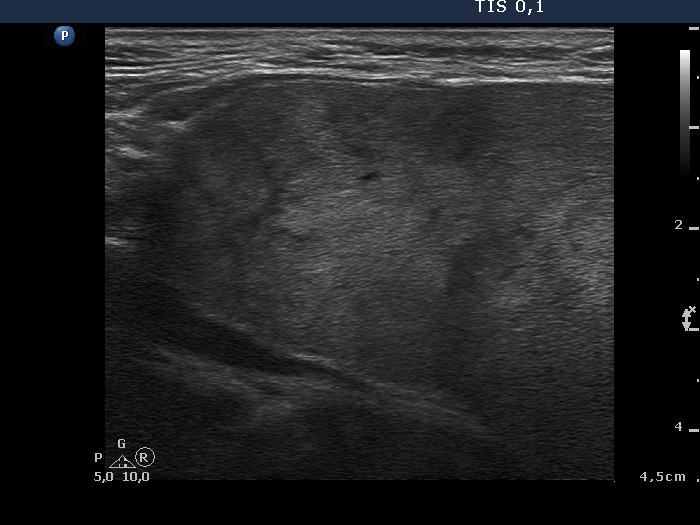

Upper part of the right lobe, longitudinal scan. A pseudonodular pattern is demonstrated.